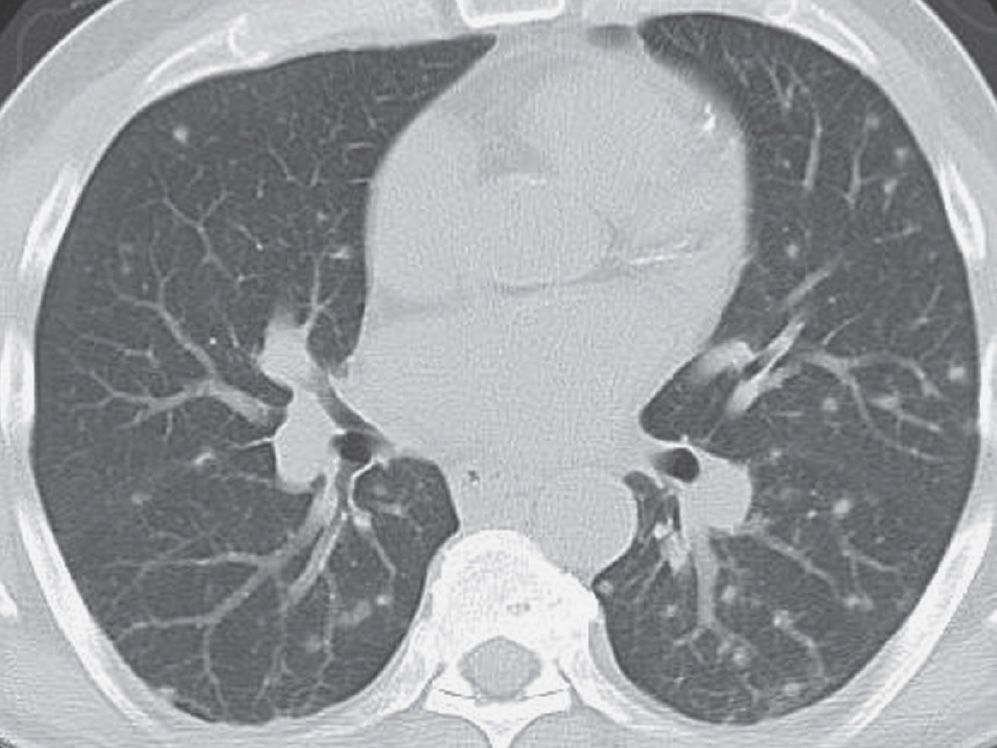

The clinical picture of aosd has been analyzed in multiple cohort studies, with varying clinical signs and symptoms. Adult onset still disease (aosd) is a rare condition characterized by elevated fever along with arthritic symptoms, elevated. Nonspecific interstitial pneumonia (3 cases), organizing pneumonia (4 cases), and. The main hrct patterns were the following:

Still Disease Lung Ct Nonspecific interstitial pneumonia (3 cases), organizing pneumonia (4 cases), and. Nonspecific interstitial pneumonia (3 cases), organizing pneumonia (4 cases), and. Adult onset still disease (aosd) is a rare condition characterized by elevated fever along with arthritic symptoms, elevated. The main hrct patterns were the following: The clinical picture of aosd has been analyzed in multiple cohort studies, with varying clinical signs and symptoms.